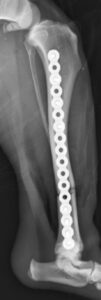

5~6歳以上の去勢手術をしていないオス犬に多い病気ですが、メス犬や去勢した犬に起こることもあります。お尻の筋肉が萎縮した結果、筋肉の隙間から直腸や膀胱が皮膚の下にとびでてしまいます。これにより便が出にくくなったり膀胱炎になったりします。手術をすることで機能回復および今後の致死的な状況を回避することができます。当院では去勢手術→結腸固定→前立腺固定→骨盤隔膜構成筋の縫縮→内閉鎖筋フラップ→浅臀筋フラップの順で通常腹側・臀部左右両側同時に行います。また老化以外に、筋肉が萎縮する原因があったり、腹圧がかかる原因があったりする場合も多いので、再発防止のためそれらの診断・治療も重要です。今回のワンちゃんも無事手術も終わり元気に退院しました。よかったね。